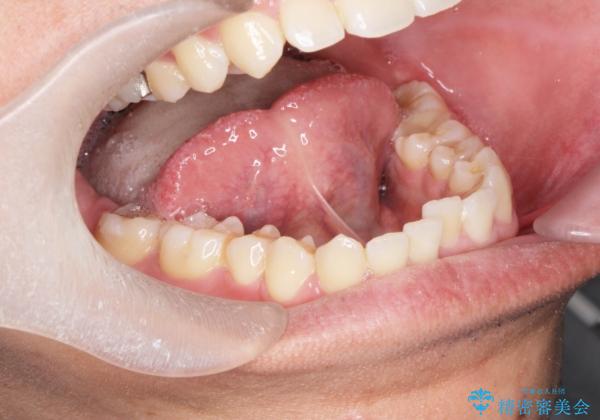

[滑舌を治したい] 舌の小帯の形成術

- ベロの動きが制限され、滑舌が悪いので改善したい。と舌小帯の形成術を希望され来院されました。

10分程度の小手術を行うことで滑舌の改善を図ります。

大幅に舌の動きが良くなり、滑舌がよくなったと喜んでいただくことができました。